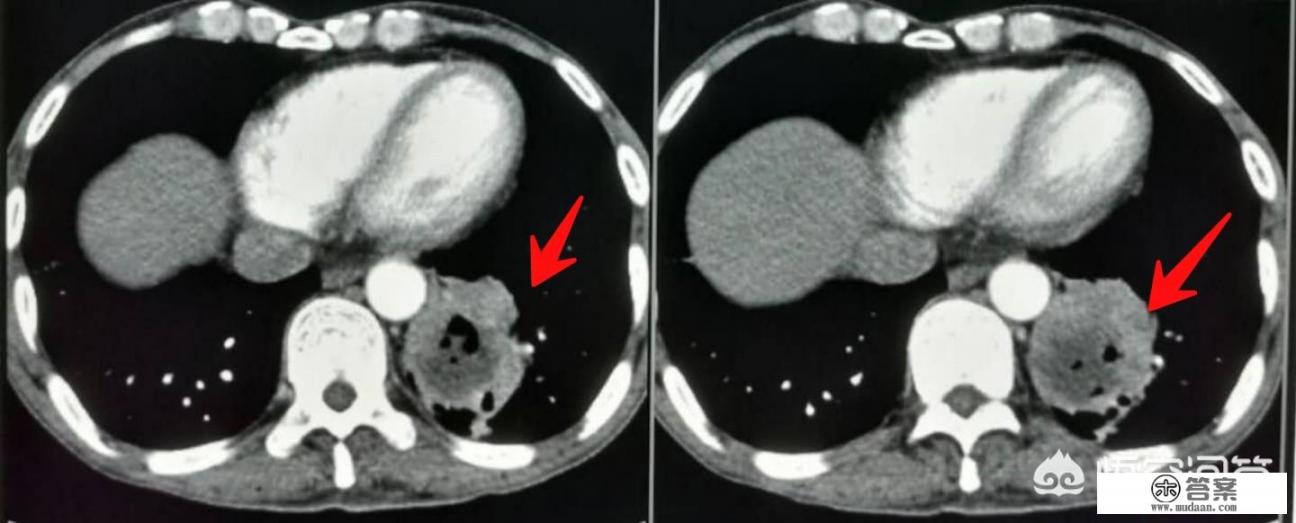

- 肝癌:有慢性肝炎或酒精性肝炎的患者一定要检查复查肝功能和肝脏超声,抽血查AFP(甲胎蛋白)有无升高,如果有肝炎和AFP升高但超声看不到肿块,也要做上腹部MR平扫加增强检查,肝炎-肝硬化-肝癌是典型的进展过程,实际工作中遇到太多这样的例子了。